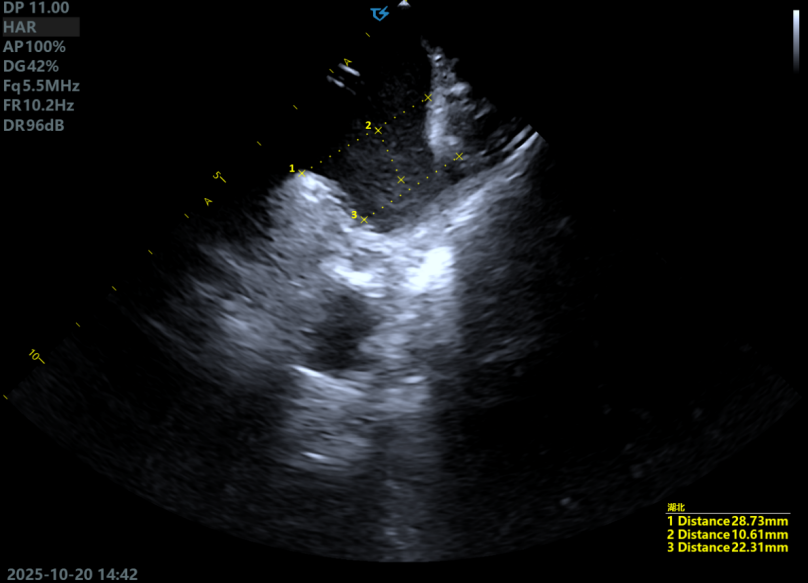

ICE下测量锚定区22.31mm,开口区28.73mm,选择LAMax 2436 Plus型号封堵器。